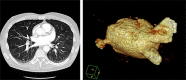

There is limited literature available regarding PV (pulmonary vein) stenosis management. Starting from its incidence, subsequent follow up using imaging technologies to monitor the success and the way of managing different groups pose varied opinions. However, with newer technological advancements and better understanding of mechanism of the atrial fibrillation ablation, the incidence of PV stenosis secondary to catheter ablation is declining. This paper highlights the current trends and future of management of PV stenosis secondary to catheter ablation for atrial fibrillation.